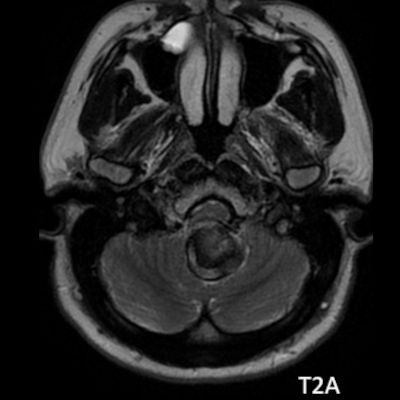

- A. Posterior fossada, T2A, T1A görüntü ve SWAN sekanslarda, 3.5 cm boyutta, düzgün sınırlı, T1A hiperintens, T2A hipointens heterojen iç yapıda kitlesel lezyon izleniyor (çember). Lezyonun serebellum ve kraniyoservikal bileşkeye bası etkisi mevcuttur (ok). Lezyon periferinde T1A, T2A ve SWAN görüntülerde hiperintens tubuler yapı bulunmaktadır (ok). Bu yapı intralezyonel “yılanvari eksantrik vasküler’’ yapıdır.

- T2 kısmen tromboze anevrizmada genellikle hipointens odaklarla heterojen, serpantin anevrizma içi damar kanalında akım boşlukları, bitişik parankimde vazojenik ödem görülebilir.

- T2 ve SWAN genellikle santral-çevresel duyarlılık artefaktları görülür.